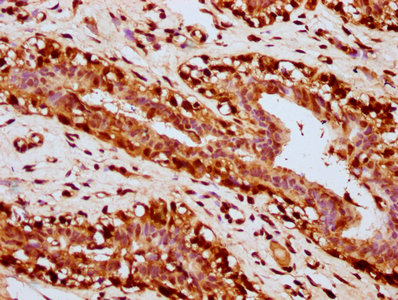

• IHC image of CSB-PA010429OA31nacHU diluted at 1:20 and staining in paraffin-embedded human breast cancer performed on a Leica BondTM system. After dewaxing and hydration, antigen retrieval was mediated by high pressure in a citrate buffer (pH 6.0). Section was blocked with 10% normal goat serum 30min at RT. Then primary antibody (1% BSA) was incubated at 4°C overnight. The primary is detected by a biotinylated secondary antibody and visualized using an HRP conjugated SP system.